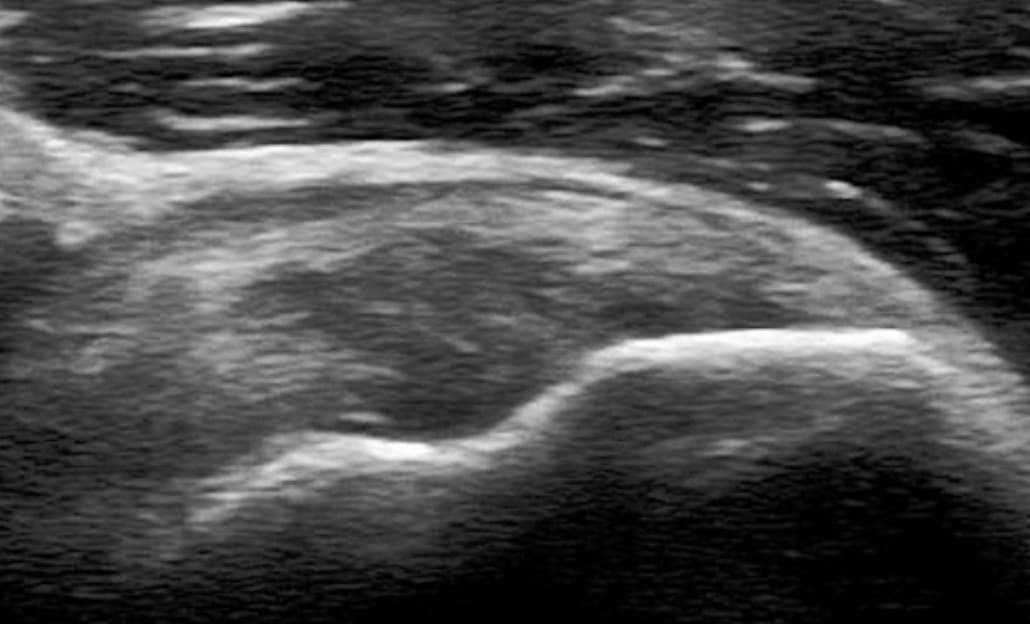

목차 반응형근육과 힘줄의 손상(급성)근육과 힘줄의 손상은 급성과 만성으로 나뉜다. 급성손상은 외부로부터의 직접 충격, 근육 수축 중에 발생하는 뻗침 손상, 관통상 등이 있다. 급성 근육손상은 임상적으로 세 가지 등급으로 나뉜다. 등급 1은 근육섬유의 손상이 없는 것이고, 등급 2는 근육의 부분 손상과 근육의 힘이 감소하는 것이며, 등급 3은 근육의 전체층 째짐이다. 근육손상의 초기에는 좌상과 출혈 때문에 낮은 에코로 보인다. 근육 전체층 찢어짐은 특징적으로 근육의 연속성이 없어지고, 끊어진 근육의 아래 끝과 이끝 사이가 벌어지게 되며, 수동적 근육운동 또는 능동적 수축에서 더욱 또렷해진다. 혈종은 시간이 지남에 따라 점점 낮은 에코로 변한다. 연조직의 출혈이 흡수되면 혈종의 크기가 작아지고, 혈종주위의 에코는 증가한다. 에코 없는 부위는 장액주머니로 남는다. 엉덩이에서 외상, 특히 벗겨진 손상에서 피하지방층과 근육 사이에 출혈이 생긴 것을 모렐-라발레 병변이라 한다. 남은 흉터는 낮은 에코로 보인다. 골화성 근염으로 흔히 불리는 이소성 골화는 낮은 에코로 보이며, 소리그림자를 동반한다. 근육의 외상 또는 해당부위의 신경손상은 근위축을 초래하여 근육의 크기가 작아지게 되고, 에코는 증가된다.  급성 근육손상의 초음파 이미지 외부로부터 받은 직접 충격에 의한 근육손상은 혈종과 다양한 정도의 근섬유 째짐을 동반한다. 반면에, 근육수축 중에 발생하는 뻗침 손상은 특징적으로 근육-힘줄 경계부 손상이고, 흔히 두 개의 관절을 건너가는 긴 근육에서 잘 생긴다. 예를 들면 넙다리뒤근육, 장딴지근안쪽갈래 등이다. 근육의 구조를 이해하는 것이 중요하다. 장딴지근안쪽갈래처럼 근육이 반깃근 구조이면 근육의 가장자리에서 근-힘줄 경계부 손상이 잘 일어난다. 근육의 구조가 휘돌 이기근 또는 깃근육이면 손상이 먼쪽 근-힘줄경계부 또는 근육 내의 중심널힘줄에서 잘 생긴다. 출혈, 염증액, 손상 후 경과시간, 손상정도 등에 따라 근-힘줄 경계부 손상은 다양한 밝기의 높은 에코로 나타난다. 소아에서 급성 힘줄손상은 힘줄이 붙는 뼈의 찢김 골절을 특히 잘 일으키고, 골절된 뼛조각은 높은 에코와 소리그림자를 가지기도 한다. 관통손상 또는 찢긴 상처는 어느 부위에라도 생길 수 있다. 근육이나 힘줄 손상은 부분 찢김, 또는 전체층 찢김으로 나눌 수 있는데, 동적검사를 하면 전체층 찢김의 소견을 더 뚜렷하게 볼 수 있다. 관통손상에서 유발된 조직의 공기는 초음파검사를 매우 어렵게 한다. 공기는 높은 에코이면서 불균질 한 소리그림자를 보인다. 손상된 근육 주위의 연조직이나 뼈를 관찰하는 것도 중요한데, 신경 등의 손상을 잘 동반하기 때문이다. 근육과 힘줄의 손상(만성)만성적 근육 및 힘줄 손상은 주로 과사용으로 발생하며, 퇴행성변화와 찢어짐이 동반될 수 있다. 손상된 힘줄에는 호산구, 섬유성 및 점액성 변화는 있으나 급성 염증세포는 없다. 그래서 힘줄염이라기보다는 힘줄증이라는 표현을 사용한다. 초음파검사에서 힘줄증은 두꺼워진 낮은 에코로 보이는데 힘줄섬유의 찢어짐은 없다. 힘줄증은 색 또는 강화도플러에서 혈류증가를 보이기도 한다. 이는 염증이라기보다는 다른 원인에 의한 광혈류 때문이다. 예를 들면 발꿈치힘줄증의 혈류는 신생혈관 때문이며 통증과 관련 있다. 힘줄증은 힘줄 찢어짐으로 진행할 수도 있다. 또 근위축이 발생하면 에코가 높아지고 근육의 크기가 감소한다. 잘못 설치된 금속고정물에 의한 인접한 힘줄의 만성적 손상은 초음파검사에서 잘 보인다. 또 동적검사를 하면 금속고정물과 힘줄의 관계를 더 잘 알 수 있다. 뼈의 손상정상적인 뼈의 표면은 부드럽고 매우 높은 에코를 가진 줄로 보이며 소리그림자를 동반한다. 또 소리그림자 안에는 소리 다시 부딪힘 인공물이 나타날 수 있다. 급성 골절의 전형적 소견은 뼈표면의 연속성 소실이며, 계단모양의 어긋난 비연속성을 보이기도 한다. 이때, 인접한 연조직에는 출혈에 의한 다양한 에코를 동반한다. 피로골절은 처음에는 뼈에 인접하여 낮은 에코의 작은 병변으로 보이며, 진행되면 골절의 전형적 소견인 계단모양 비연속성으로 바뀌거나, 아니면 높은 에코의 애벌뼈형성으로 변화한다. 탐촉자로 골절부위를 누르면 특징적인 날카로운 누름통증을 일으키기도 한다. 이런 환자는 흔히 국소통증을 가지므로, 검사를 끝내기 전에 환자에게 "혹시 그런 통증이 있는지?"를 물어보면, 임상의사나 초음파 검사자가 놓친 병변을 추가로 찾는데 도움이 된다. 힘줄이나 인대가 붙는 부위의 찢김 골절에서 작은 뼈 조각은 소리그림자를 동반하는데 그림자의 정도는 다양한다. 어린이에서 뼈 성장판의 불규칙과 비대칭적 넓어짐, 날카로운 누름통증이 있을 때에는 성정판골절을 시사한다. 뼈겉돌기는 관절에서 뼈끝에 생기며, 날카로운 누름통증이 없다. 단순촬영을 참조하는 것이 좋다. 초음파에서 발견되는 골절의 대부분은 진료의사가 의심하지 않았던 골절이다. 왜냐하면, 대부분의 환자에서 단순촬영이 정상이어서, 초음파검사로 연조직과 관절의 이상을 알고자 검사를 의뢰하기 때문이다. 이러한 예는 발에서 종종 보이며, 단순촬영에서는 여려 뼈가 겹쳐져 보여 관찰이 힘들 수 있다. 위팔뼈 몸 쪽에서 큰 거친 면 골절은 단순촬영사진에서 놓치는 경우가 흔히 생긴다. 왜냐하면, 환자의 팔이 부적절한 자세로 놓인 상태에서 촬영을 하게 되기 때문이다. 갈비뼈(늑골) 골절의 진단에는 단순촬영보다 초음파가 더 효과적이라는 보고도 있다. 골절이 치유되면서 초기에 보이는 낮은 에코의 애벌뼈는 높은 에코의 딱딱한 애벌뼈로 바뀌고, 이후 애벌뼈가 골절선을 덮어서 뼈가 연결된다. 이러한 소견은 팔다리늘림술에서도 보인다. 초음파검사로 새 뼈의 형성을 단순촬영보다 더 빨리 볼 수 있다. 정강뼈(경골) 골절의 불유합의 진단, 금속나사 고정술에서도 초음파검사가 이용된다. 금속나사의 표면에 애벌뼈가 없으면 나사의 끝이 높은 에코로 남게 되는데 이런 소견도 단순촬영보다 더 일찍 초음파검사에서 볼 수 있다. 그밖에 어린이에서 위팔뼈 먼 쪽뼈끝이나 갈비물렁뼈(늑골연골)의 관찰에도 이용한다. 반응형